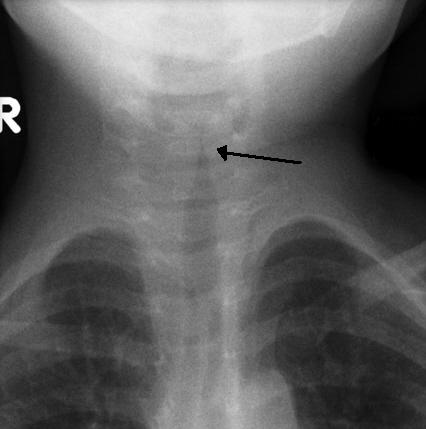

크룹(후두기관지염)은 성대의 바이러스 감염으로, 일반적으로 5~6일 지속된다. 주요 증상은 짖는 듯한 기침과 저열이다. X선 사진에서 크룹은 기관의 협착을 나타내는 "첨탑 징후"로 확인할 수 있다.